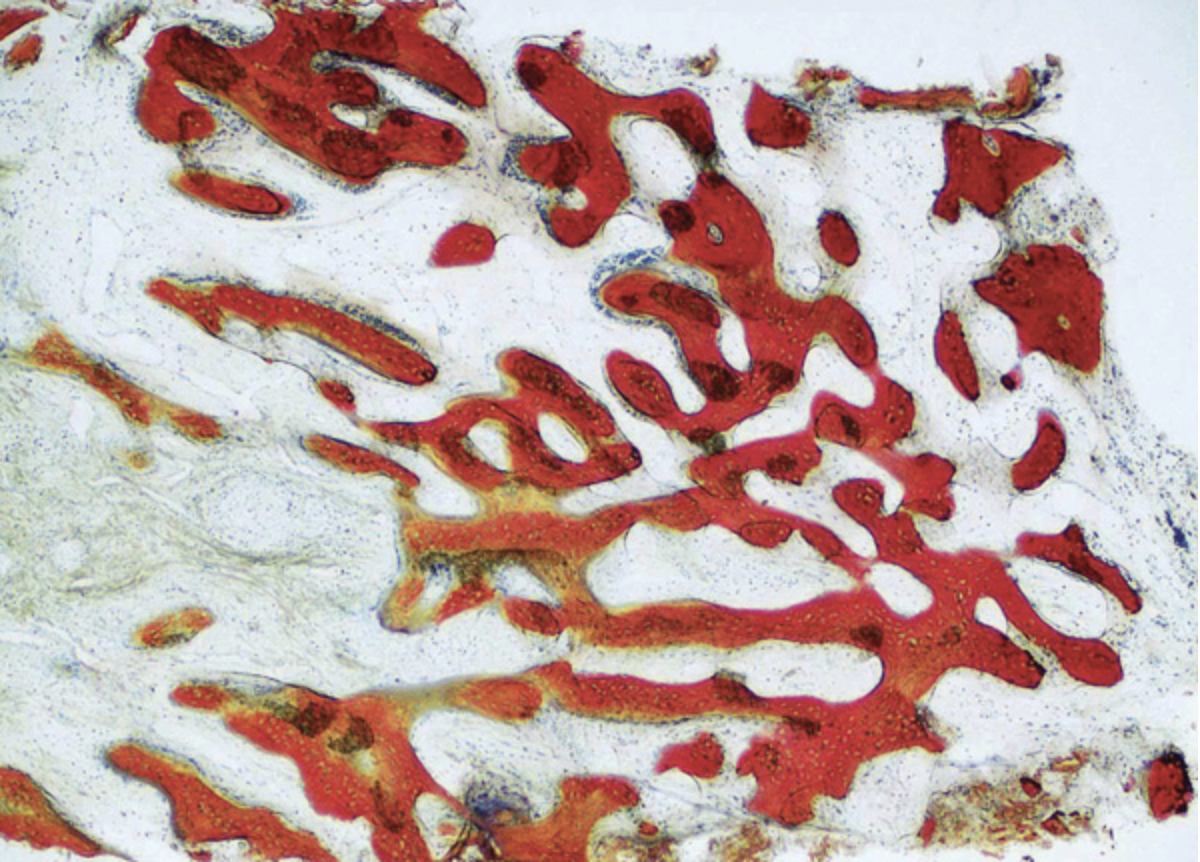

The patient shown in Figure 1 had presented after significant endodontic-related abscesses reduced the height of both buccal and lingual plates of bone. Covering the biphasic calcium sulfate (BPCS) graft with a dense polytetraflouroethylene (PTFE) barrier for 3 weeks enhanced healing in the site. Clinically, it is apparent that the ridge volume was maintained over 5 years and supported keratinized tissue (Figure 2). Most importantly, there was, on histologic evaluation, 58% vital bone, with no remnants of the bone replacement graft material (Figure 3).

Fig 3. Although the graft had only been in situ for 4 months, the resulting histology demonstrated 58% vital bone, no remnants of graft material, and a dense trabecular nature. (Histology sample provided by Dr. Rohrer and Mr. Prasad.)

Figure 3